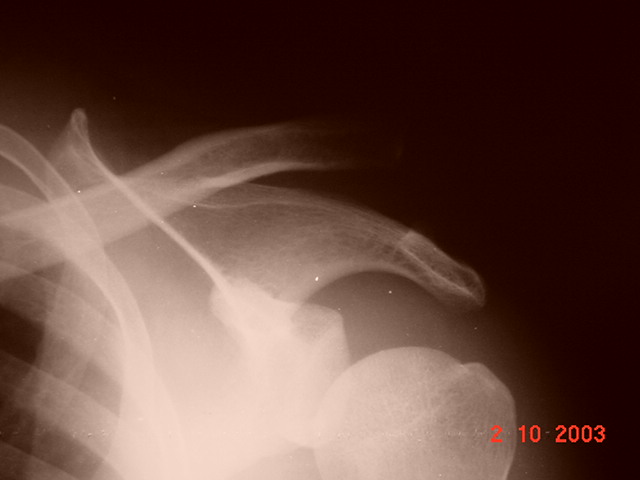

LUXACION ACROMIO CLAVICULAR COMPLETA

Paciente del sexo masculino, quien sufre accidente en motocicleta.

Traumatismo con impacto directo sobre el hombro izquierdo.

Luxación acromio clavicular completa.